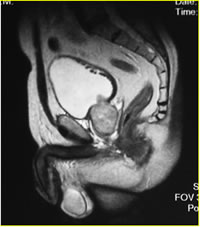

Рак полового члена по мрт - фото презентация